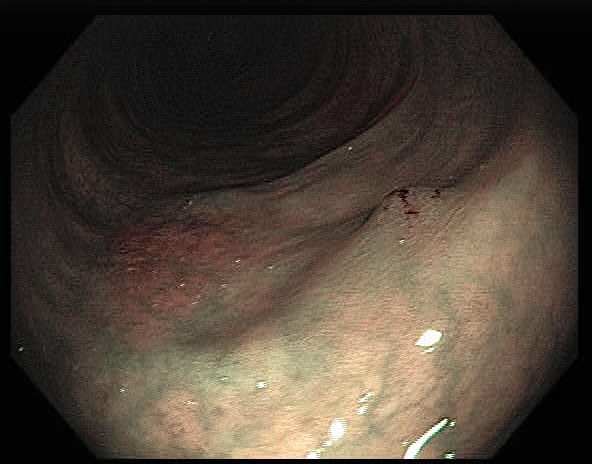

Colonoscopy is the main diagnostic procedure to detect and recognize polyps located on colorectal walls. The accurate detection and correct classification depend on the skills and experience of the endoscopists, however, even for experienced endoscopists, working on conventional colonoscopy for long hours leads to mental and physical fatigue and degraded analysis and diagnosis. Other factors that may affect the classification results include varying illumination conditions, variant texture and appearance, and occlusion. Moreover, different types of polyps are hard to differentiate since they may exhibit a very similar appearance with a subtle difference, as shown in Fig 1. It requires a thorough examination of fine details to distinguish one category form the other. Therefore, an accurate and effective automatic computer-aided system for colonoscopy is required to help endoscopists to detect and classify the type of polyps. This automated recognition mechanism can also be used as a second opinion to determine whether a further biopsy is required for diagnosis, which in turn will greatly reduce the cost of diagnosis. In addition, such an intelligent system can also be used as an educational resource for gastroenterology trainees to reduce the learning curve and cost.